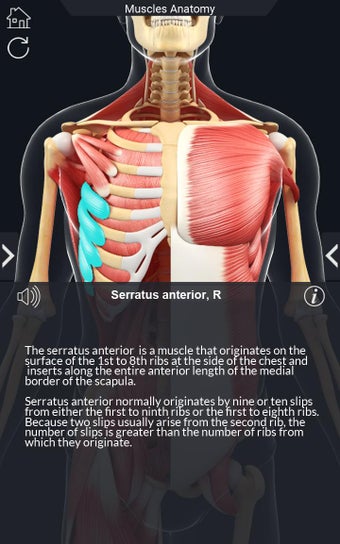

Det finns mycket detaljer tillgängliga för varje muskel, vilket gör det till ett utmärkt verktyg för medicinstudenter.

Det finns många verktyg tillgängliga för varje muskel, inklusive:

- Göm och visa varje muskel separat.